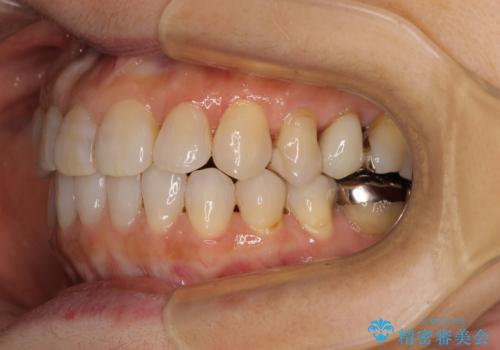

前歯の突出感と上下の隙間 インビザラインによる矯正治療

- 前歯の上下スペースと前歯の隙間を気にして来院された患者様です。

インビザラインにより上下の前歯の隙間を閉じながら、IPRを用いて口元の突出感を合わせて改善していくこととしました。

上下の隙間に舌が入り込むことが、すきっ歯やオープンバイトの原因であったため、舌の筋肉のトレーニングも並行して行い、後戻りの抑制を図りました。